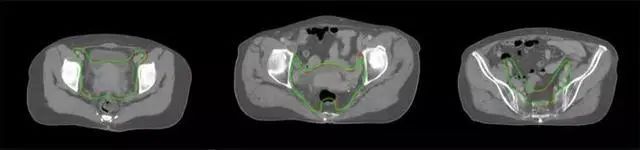

四、放射治療智能勾畫軟件

放射治療,簡(jiǎn)稱放療,是治療腫瘤主要手段之一,利用放射線破壞照射區(qū)(靶區(qū))的細(xì)胞,使腫瘤細(xì)胞停止分裂直至死亡,醫(yī)生通常把放射治療形象的比喻為“打靶”,放療前精準(zhǔn)勾畫腫瘤靶區(qū)范圍是腫瘤放射治療的關(guān)鍵步驟。傳統(tǒng)的靶區(qū)勾畫醫(yī)生會(huì)根據(jù)患者多張CT、MRI影像片憑借經(jīng)驗(yàn)進(jìn)行,比較耗時(shí),治療的病人數(shù)量也有限,且靶區(qū)勾畫缺少行業(yè)統(tǒng)一的規(guī)范和標(biāo)準(zhǔn),無(wú)法達(dá)到同質(zhì)化,勾畫精確度不理想。

技術(shù)原理

基于深度學(xué)習(xí)人工智能的放療靶區(qū)智能勾畫技術(shù)和自動(dòng)計(jì)劃技術(shù),基于全面的市場(chǎng)調(diào)研和臨床專業(yè)意見(jiàn),采用獨(dú)創(chuàng)的基于小樣本量的人工智能算法,實(shí)現(xiàn)放療靶區(qū)和危及器官的快速全自動(dòng)勾畫。

產(chǎn)品優(yōu)勢(shì)

縮短至幾分鐘內(nèi)便可完成,大幅提升了放療效率,且人工智能平臺(tái)完成的靶區(qū)勾畫可基本滿足臨床醫(yī)生需求,專家只需審核時(shí)細(xì)微調(diào)整,可顯著提高靶區(qū)勾畫的規(guī)范化及精準(zhǔn)度,讓放療智能化,標(biāo)準(zhǔn)化??筛采w食管癌、鼻咽癌、直腸癌、宮頸癌、肺癌等多種病種。